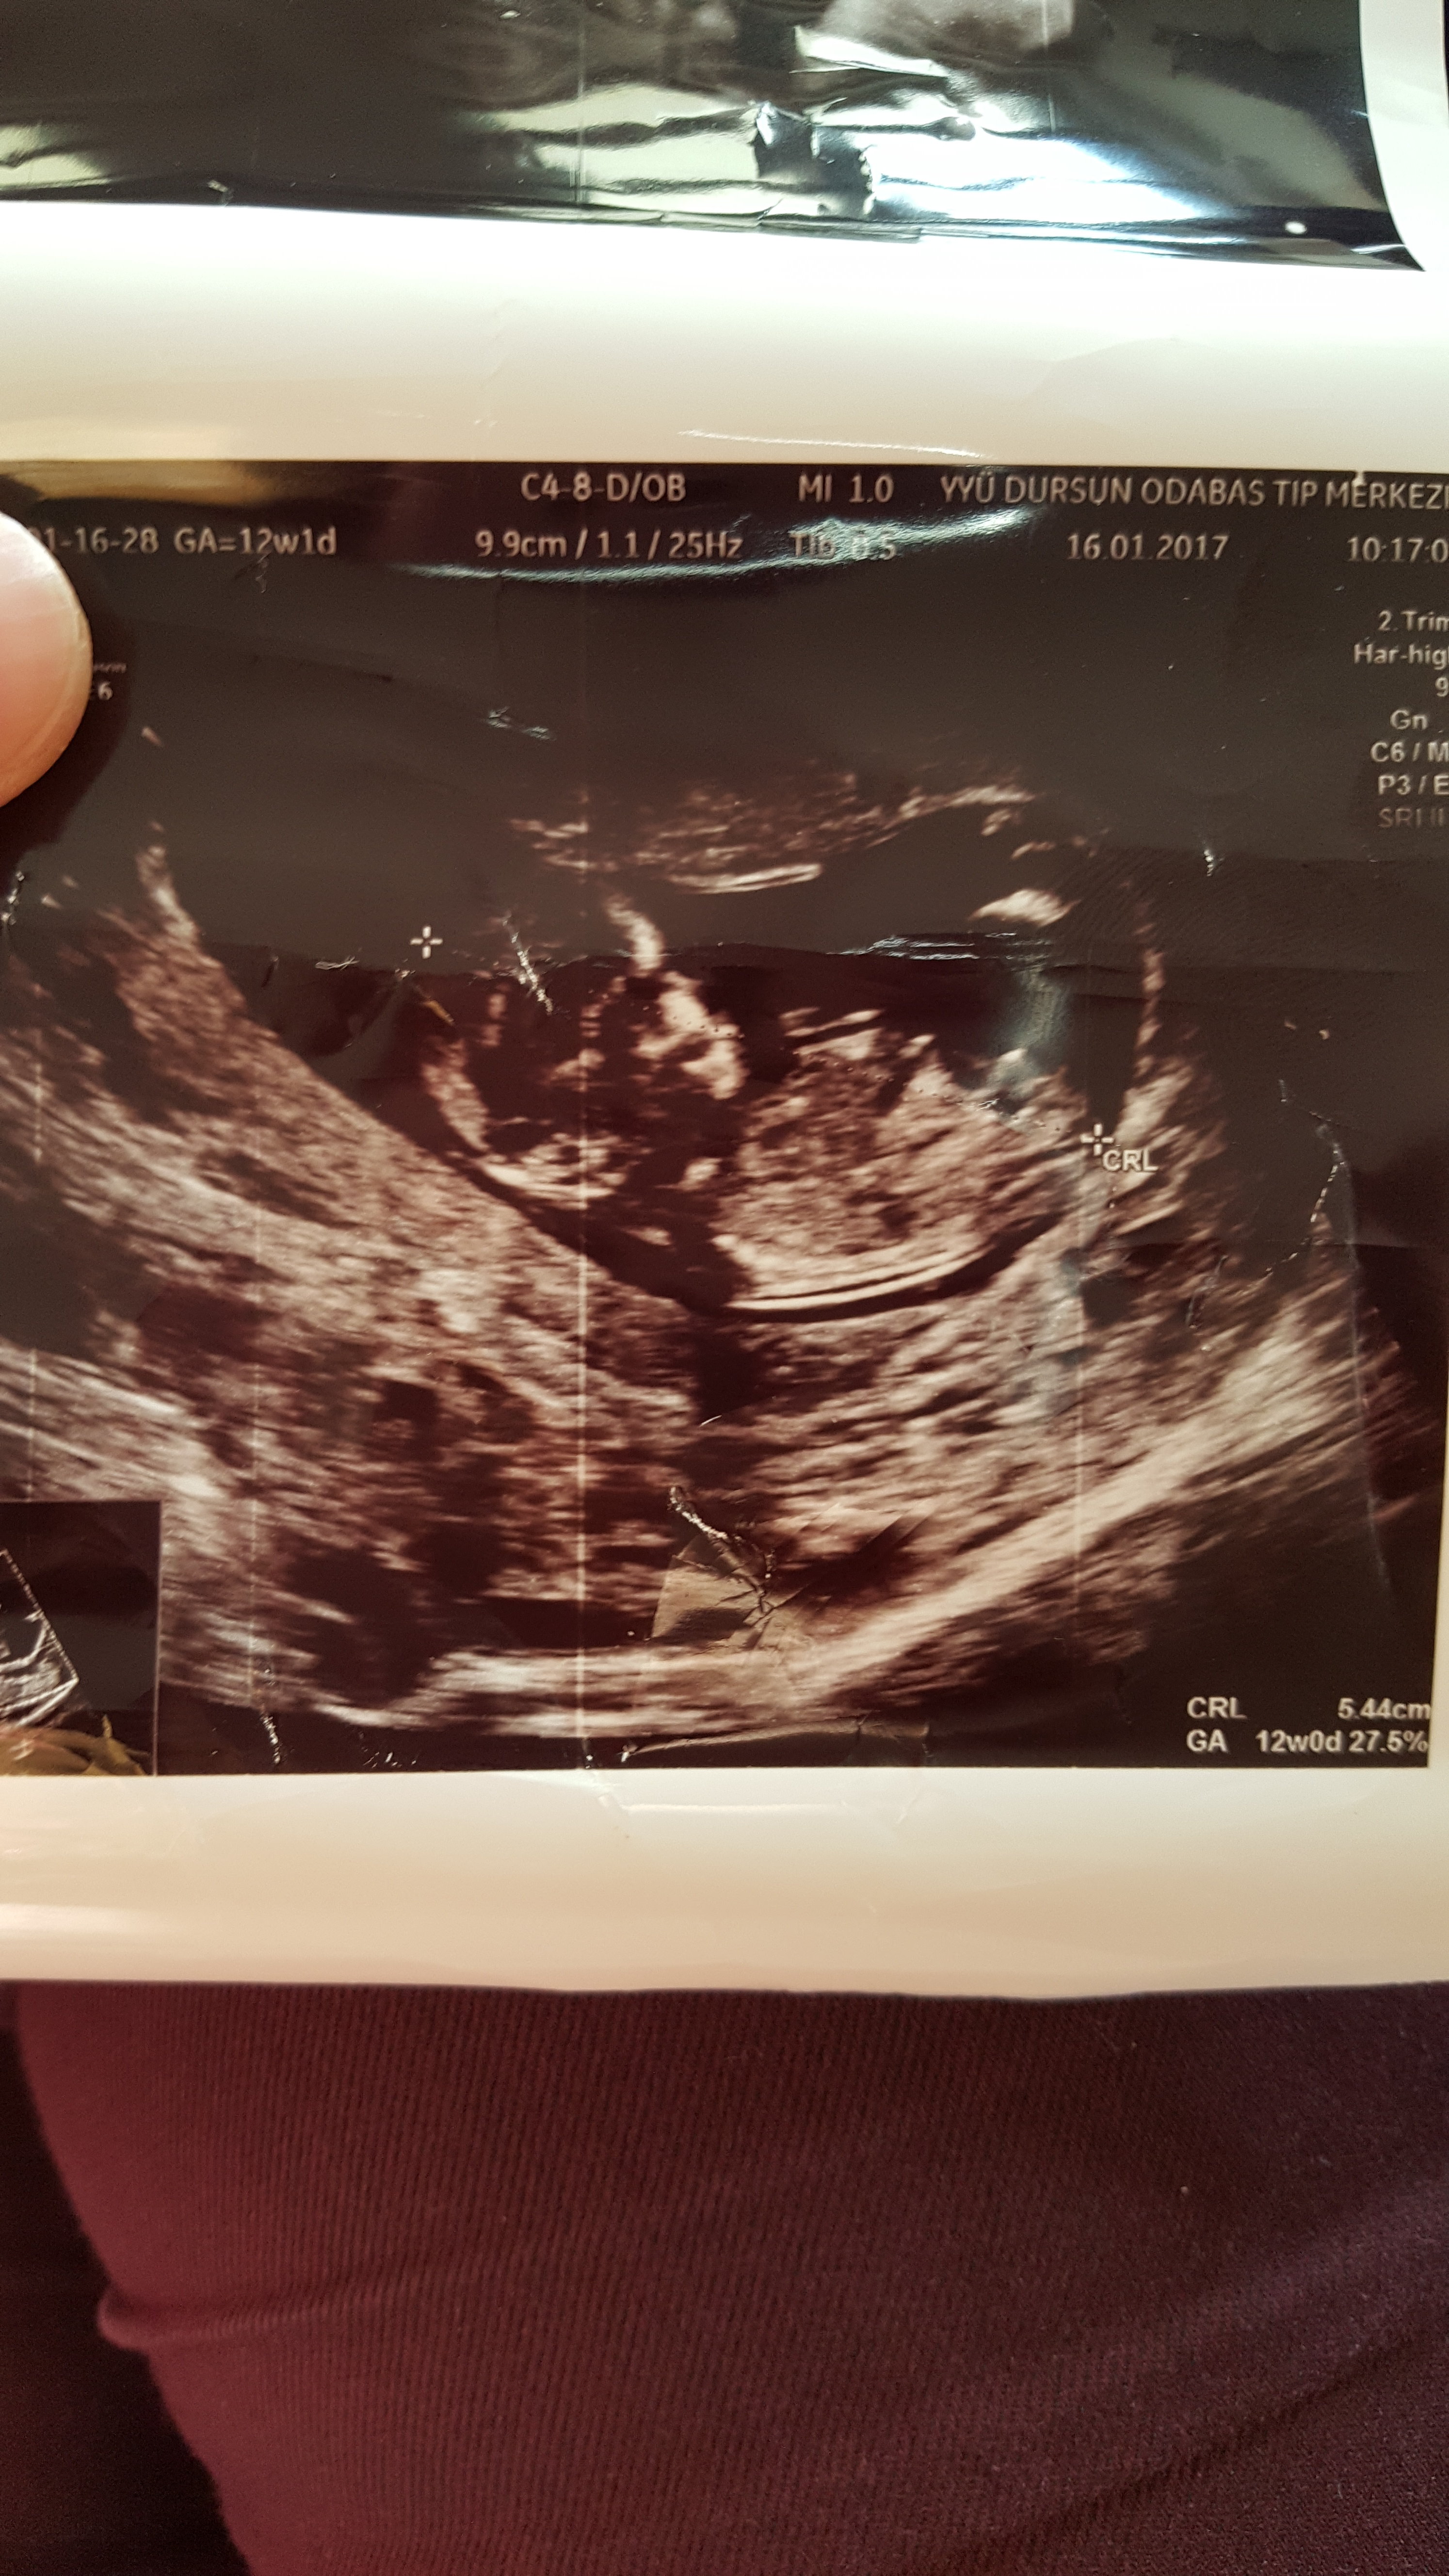

E Efsa35 Yeni Üye Üye 20 Ocak 2017 #144 Merhaba benim bebiş 12 haftalık cinsiyeti ne olabilir şimdiden teşekkür ederim

Sevimli cadı Daimi Üye Üye 20 Ocak 2017 #145 merhaba görsel net olmadığı için değerlendirme yapamıycam. Allah hayırlı doğumlar nasip etsin